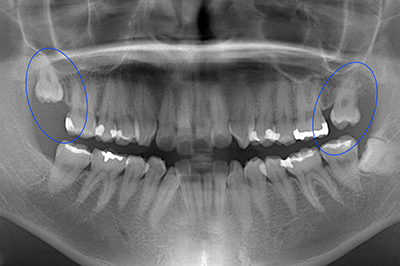

1.お口の中の診察しレントゲンやCT検査を行います。 検査により親知らずが神経に接している場合は、抜歯によって神経損傷のリスクがあるため、大学病院に紹介するか、2回抜歯法にて安全に抜歯をおこないます。

CT検査にて親知らずと神経が接してしる

親知らずを移植したケース2

第二大臼歯のな根が折れており抜歯と診断

第一大臼歯がすでに欠損しているのでこのままだと奥歯が2本失ってしまう為、第二大臼歯に親知らずを移植し、第一大臼歯部はインプラント治療を計画した。

治療期間 1年

費用 60万円(インプラント45万 / 歯の移植15万)

| メリット | 親知らずを移植することでインプラントの本数を減らして費用を抑えることができる |

|---|---|

| デメリット | 歯の移植はインプラントに比べて成功率が低い |